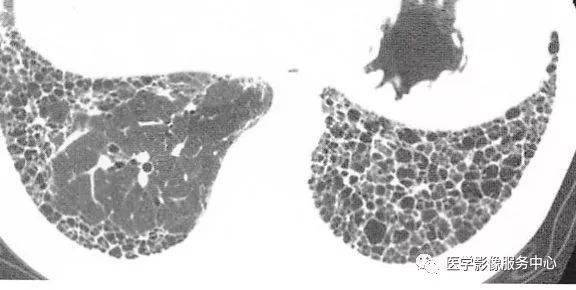

为急性耶氏孢子菌肺炎的肺气囊及磨玻璃影.

肺气肿肺大泡肺气囊不一样

肺气囊